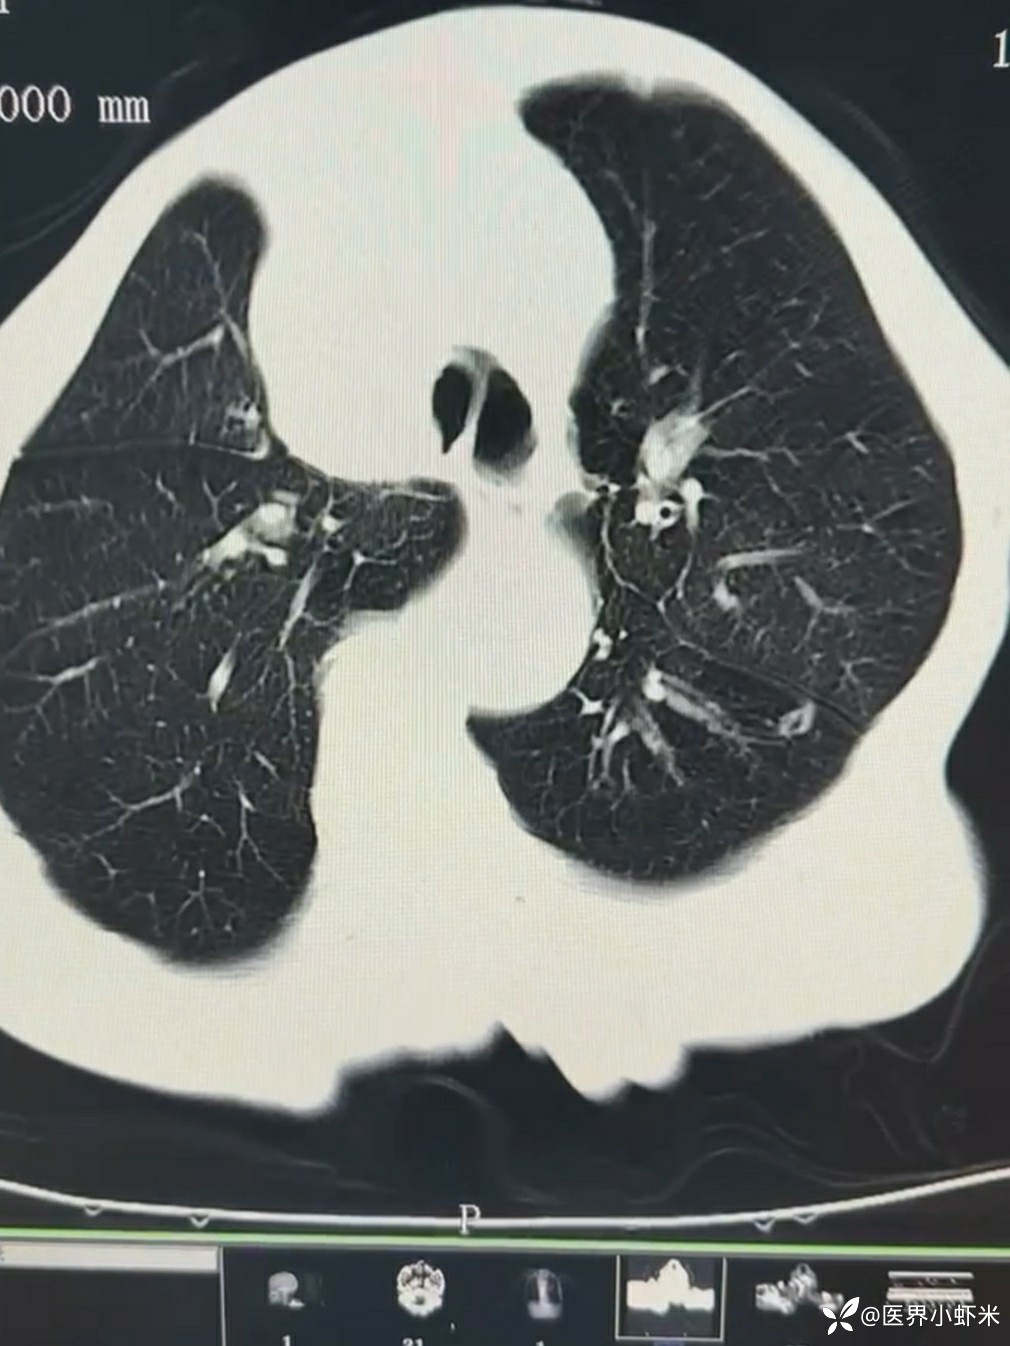

目前考虑:1.中央型肺癌伴2.肝继发恶性肿瘤?2.左丘脑继发恶性肿瘤?3.左丘脑出血?4.肾功能不全5.肝功能异常6右肾萎缩7.肺部感染8.慢性阻塞性肺病7.高血压3级(极高危)。